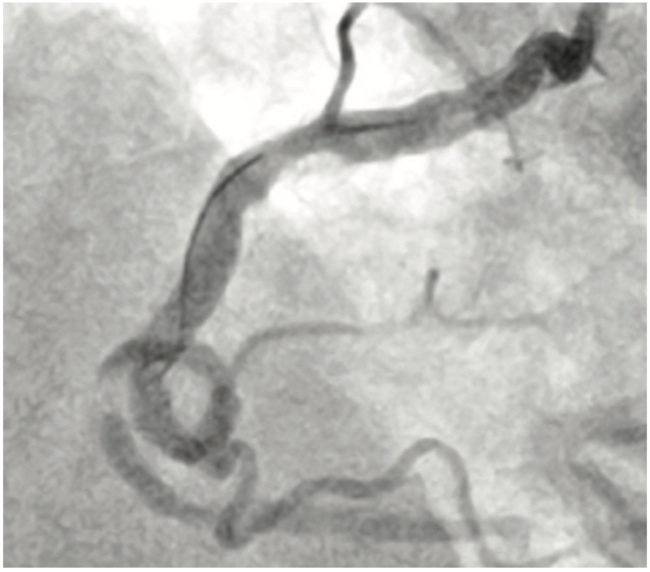

TAKERU PTCA Balloon Dilatation Catheters have been recently launched by Terumo. In this report, we summarize our initial experience with the TAKERU balloon catheter. Since July 1, 2019, we have used these balloon catheters in over 40 cases.

The 1.5 mm balloon catheter has a single midpoint Platinum-Iridium radiopaque marker (larger diameter balloon catheters have two markers) and is equipped with a 108 cm stainless steel proximal shaft and 21 cm stainless steel core middle shaft. The unique feature of this balloon catheter is the 23 cm hydrophilic coating that allows excellent tracking ability. The TAKERU 1.5 balloon catheter’s entry profile is 0.43 mm, relatively larger compared to the Sprinter Legend (1.25 mm) (Medtronic). However, the TAKERU balloon catheter has greater pushability based on bench testing results.